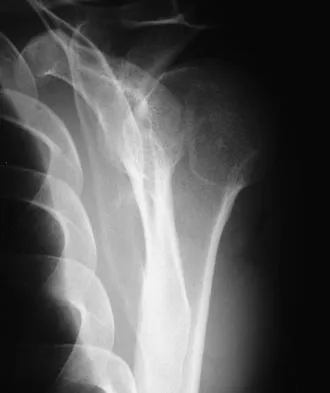

A 64-year-old man who was involved in a high-speed motor vehicle accident 6 weeks ago has been in the ICU with a closed head injury. Examination reveals that his range of motion for external rotation to the side is -30 degrees. Radiographs are shown in Figures 28a and 28b. What is the most likely diagnosis?

Explanation